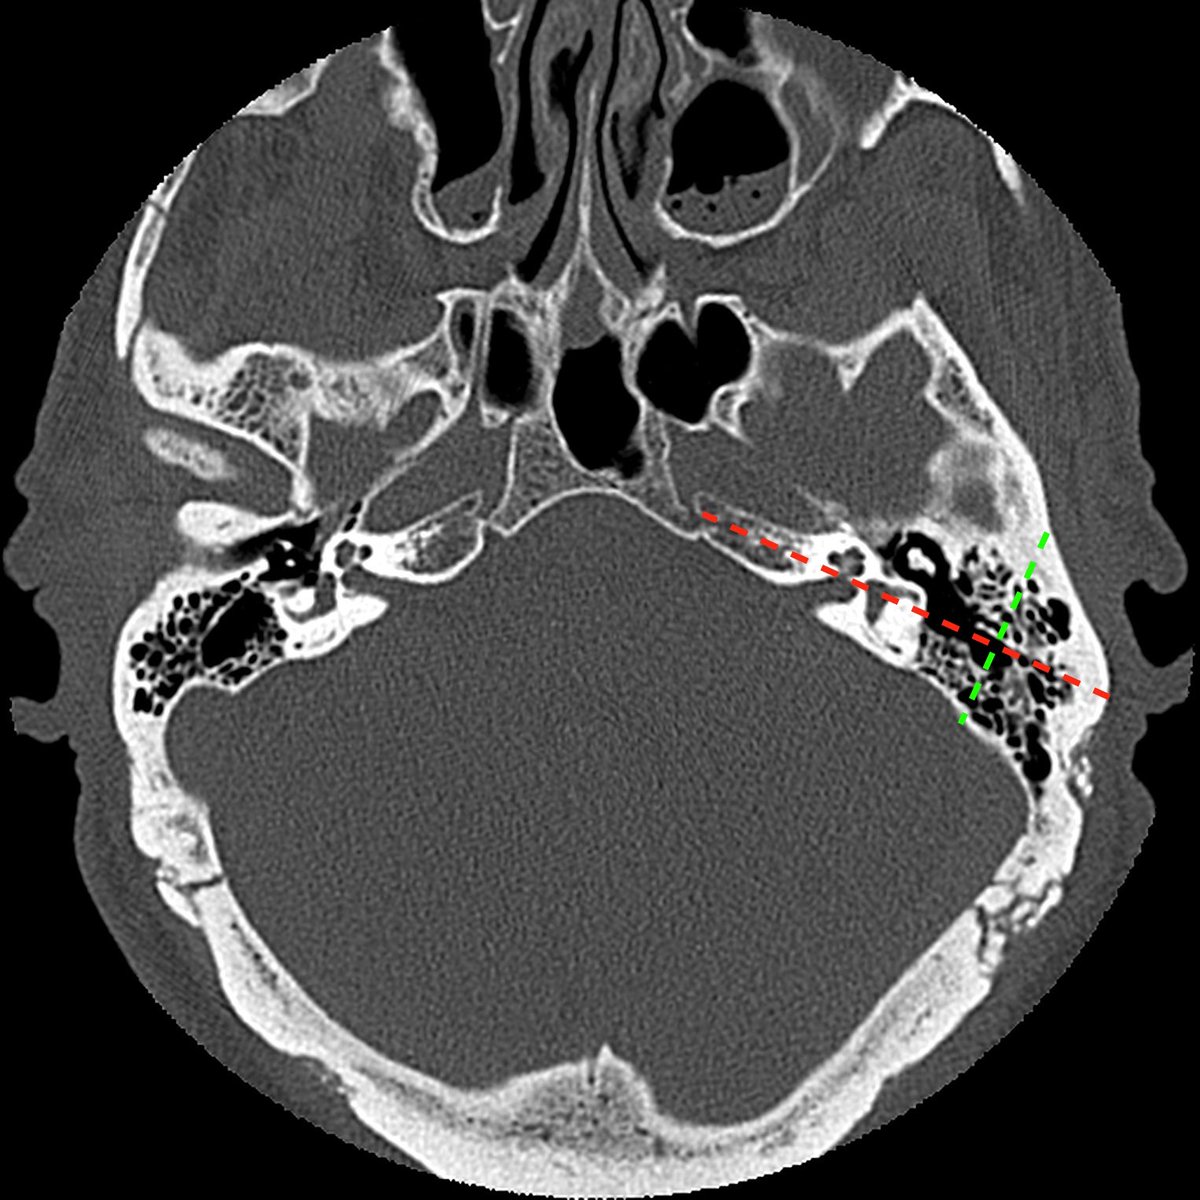

٤-عمل #أشعة مقطعية (CT) ورنين مغناطيسي (MRI) على المخ والاذن والتي تعطي معلومات عن حالة المخ وتشريح #القوقعة والعصب السمعي.